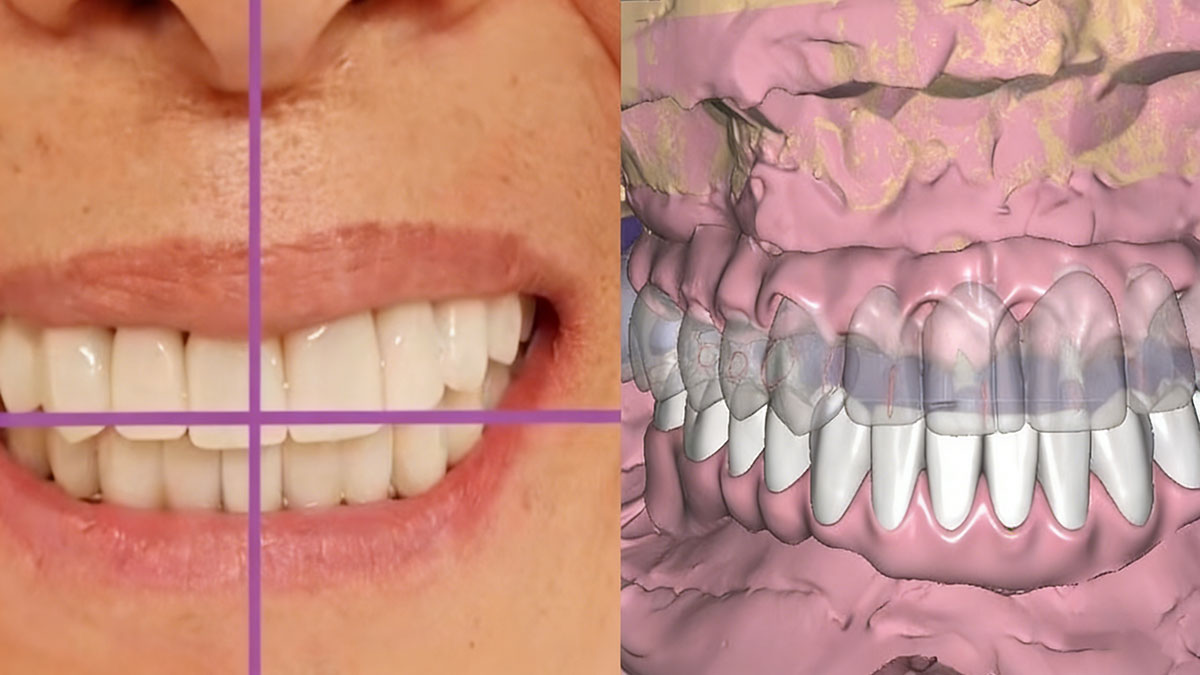

As requested, we sent designs of the titanium bar and temporary bridges. After our doctor’s approval, we milled the titanium bar and made temporary bridges in 7 days. However, about 10 days later, we received a picture. Our doctor said that the fitting and occlusion were good, but the mid-line was off.

3. Re-design with new bite

About 5 days later, we received stone models, the titanium bars, temporary bridges, and a new bite registration. With the help of pictures and new bite registration from our doctor, we re-designed titanium bars and temporary bridges.